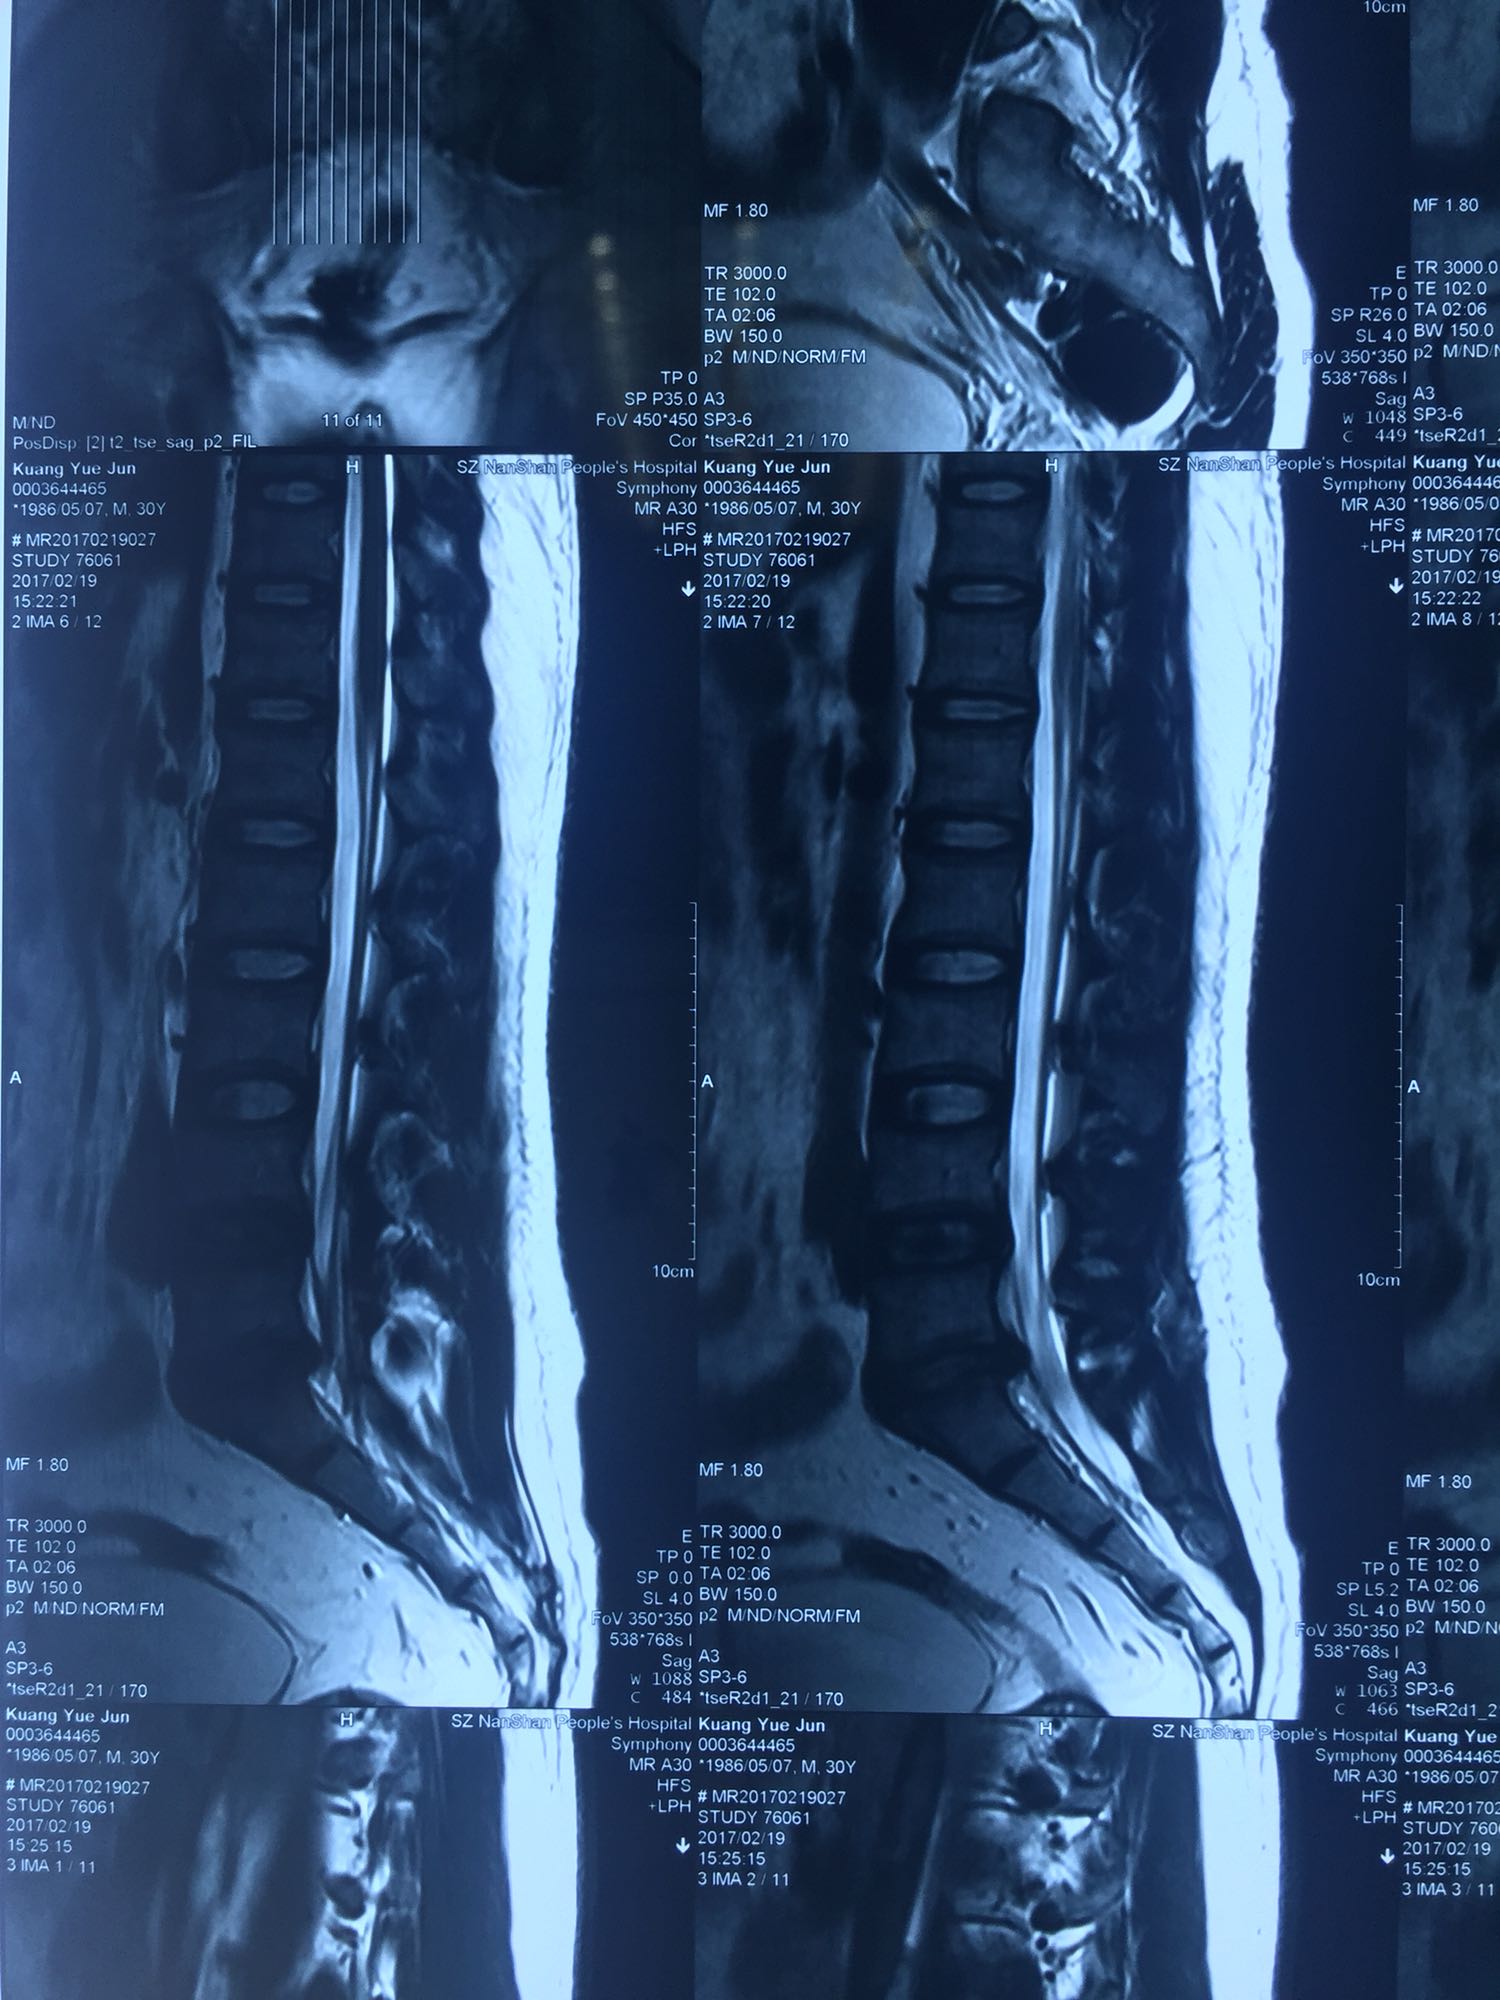

邝X军,男性,30岁,因左下肢疼痛1天而入院。 1天前无明显诱因出现左下肢疼痛,程度较重,难以忍受,伴有行走困难。

腰骶部肌紧张,腰5骶1棘间及左侧椎旁有压痛及放散痛,左侧坐骨神经出孔处有压痛及放散痛,左侧足背外侧及足底部皮肤感觉麻木,左侧直腿抬高试验阳性(30度)。

诊断:腰5骶1椎间盘突出症 治疗方案:椎间孔镜下经椎板间入路髓核摘除术